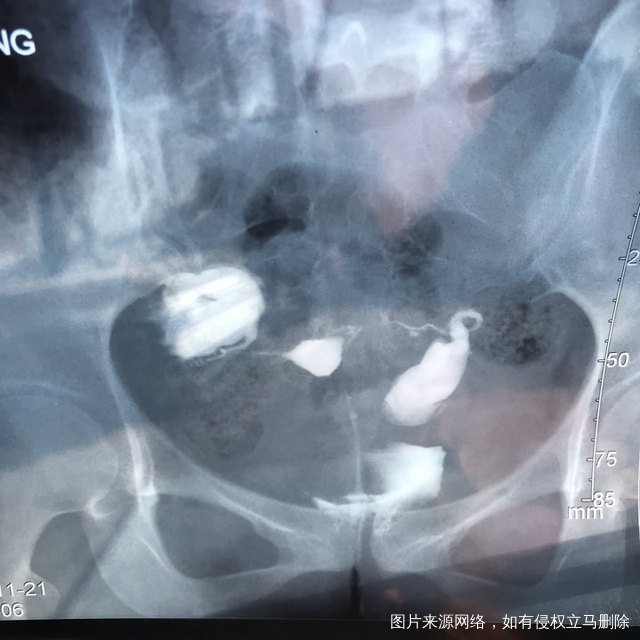

麻烦各位教授给我看看输卵管造影片子,谢谢了🙏